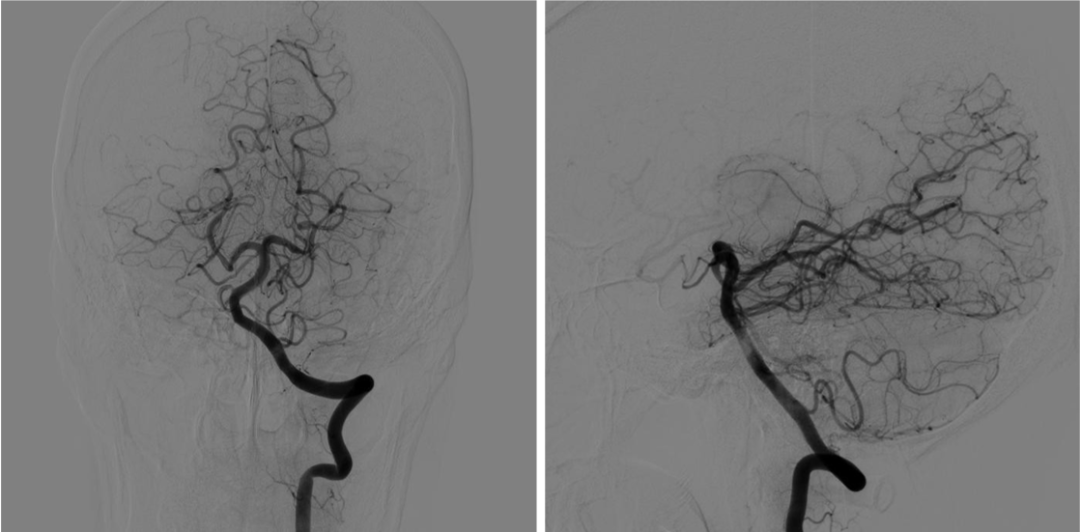

右侧椎动脉超选造影

左侧椎动脉超选造影